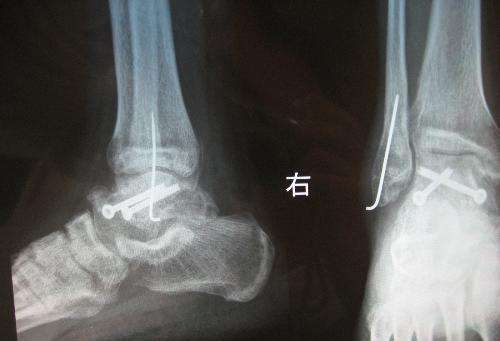

脚踝骨折

脚踝骨折的病因及影响骨折恢复几个因素